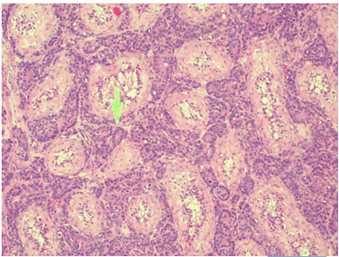

Figure 1 Albuginea, Seminiferous tubules. (100x).

Figure 4 Infiltration by glands in the testicular parenchyma, with entrapment of the tubules.

Histopathology is key for the diagnosis of testicular metastasis. In most cases, the histology of metastatic testicular tumor matches the primary lesion, which in the context of prostate cancer most commonly correspond to adenocarcinoma.3 In some of our cases, the pathology showed glandular, cribose or isolated cells invading the interstitium without affecting the seminiferous tubules, as well as lymphovascular invasion with intertubular growth. The immunohistochemical markers present were those found in prostate cancer such as PSA, PSAP, CKAE1/AE3, NKX 3.1.11